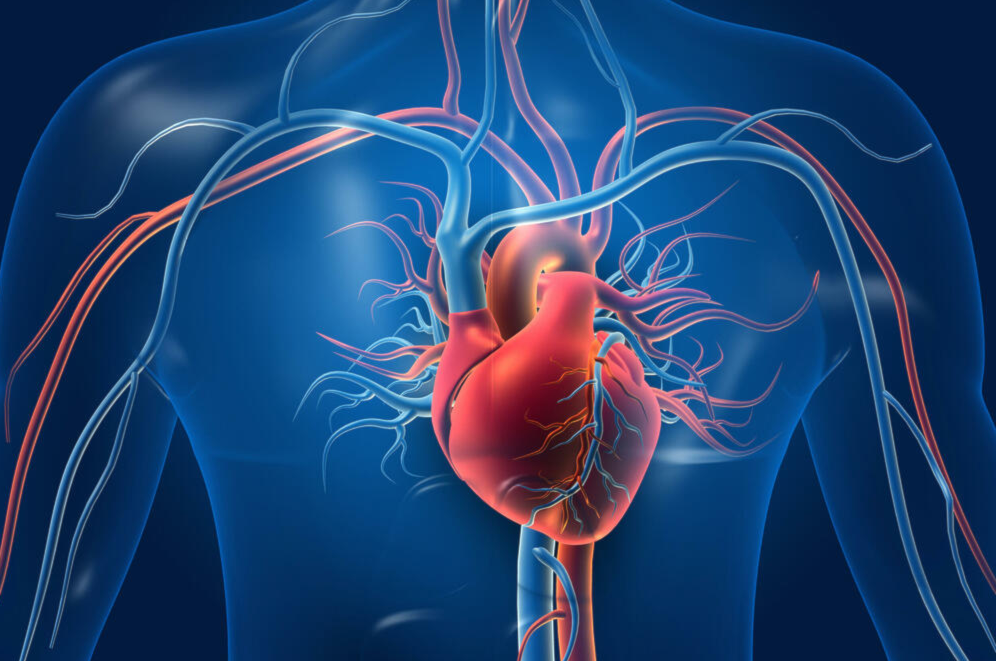

علماء روس يطورون أغشية مرنة، بدلاً من أشباه الموصلات والمعادن التقليدية في مجال الإلكترونيات النانوية، ويمكن استخدام هذه الأغشية الكربونية التي تتميز بقدرتها على التمدد كـ"رقع للقلب".

ابتكر فريق بحثي من فيزيائيي جامعة "ساراتوف" الحكومية الروسية، غشاءً يتميز بخصائص فريدة للإلكترونيات الكربونية المرنة، حيث يحتفظ هذا الغشاء بخصائصه حتى عند تمدده بنسبة تصل إلى 40%، ويمكن استخدامه في تطبيقات طبية.

كما تمهّد هذه الأغشية الطريق لإنتاج إلكترونيات مرنة وشفافة قابلة للارتداء، وبفضل قابليتها للتمدد، تتبع هذه المادة حركات الجسم من دون أن تفقد موصليتها.

علاوةً على ذلك، يمكن استخدام هذه الأغشية كـ"رقع للقلب"، فمع كل انقباضة لعضلة القلب، تتمدد المادة مع الحفاظ على بنيتها، ما يضمن استقرار عمل "الطرف الاصطناعي".